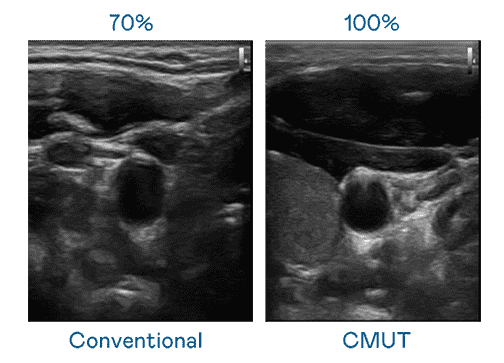

CMUT 技术是一种用电容式微机电元件来产生超音波讯号的技术。。与传统 PZT 压电式技术相比,,CMUT 频宽增加 30%,,更宽频的超音波讯号让影像解析度大幅提升,,,,是实现高影像品质医疗超音波扫描、、促进精准医疗发展的关键技术。。。。

大频宽带来超清晰影像

超音波影像的解析度高低,,首先取决于探头能发出的讯号频宽。。。。银河集团 CMUT 可提供高清晰的超音波讯号,,,,提供高频宽、、、、高灵敏度、、、影像纹理细节更高的超音波影像,,,,协助医护人员缩短影像判读时间及利用精准的医疗影像进行诊断。。。。